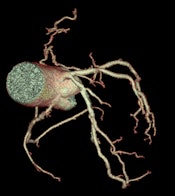

With its latest technology on display here in Vienna, GE Healthcare aims to tackle some of the specific challenges faced in conducting CT examinations on cardiac patients, including coronary motion, high heart rates, plaque composition, and accurate perfusion. Its Discovery CT750 HD Freedom Edition offers capabilities that could "change the rules" of cardiac CT. Based on the FREEdom (Fast Registered Energies and ECG) technologies, the system is designed to offer major innovations, including intelligent motion correction, improvements in calcium visualization, plaque material composition assessment, and more accurate perfusion calculations.